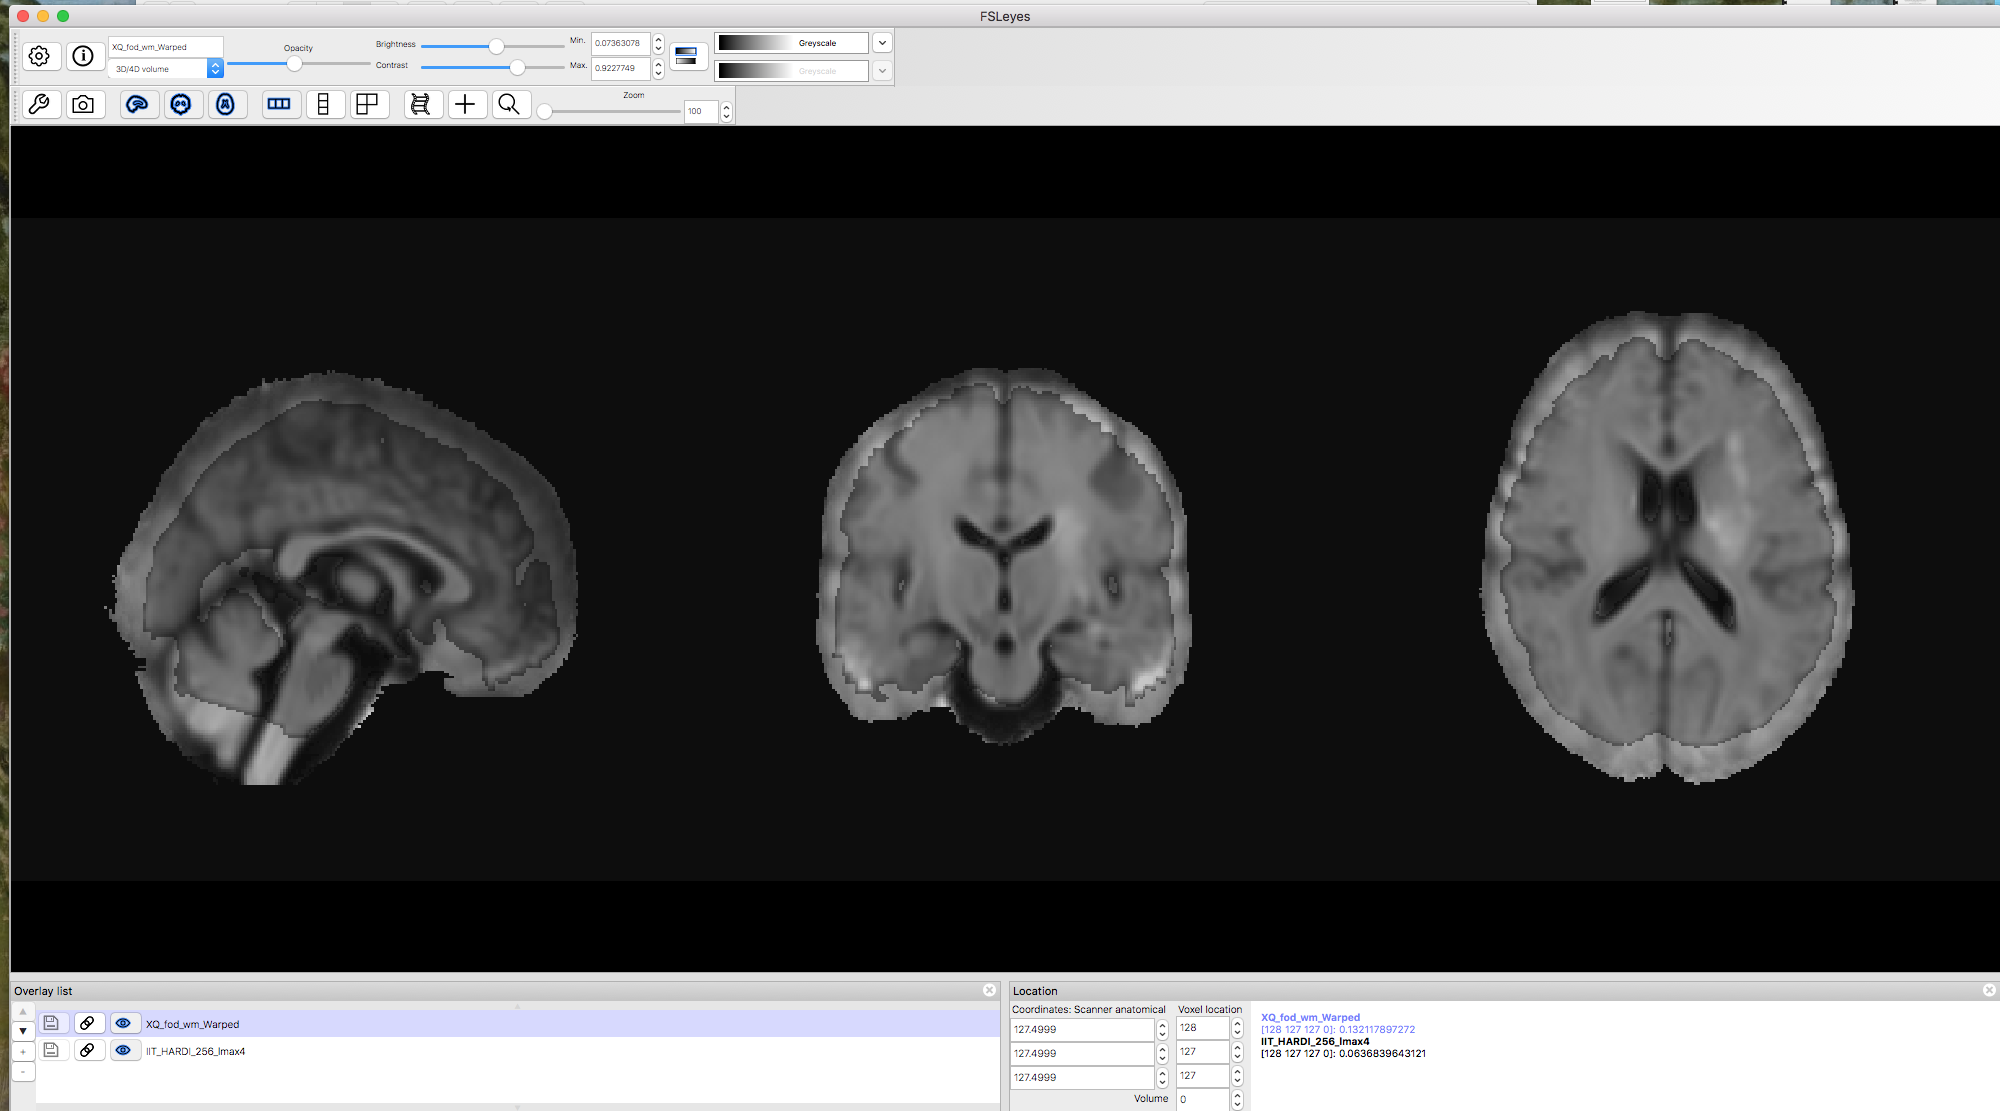

I tried what you suggested, but it still didn't help much. I've attached a screenshot of the registered FOD and the IIT HARDI template in FSLview (the IIT HARDI is overlaid on the FOD and transparent 30%). As you can see, there is still a shrinkage of the cortex. It's very strange...